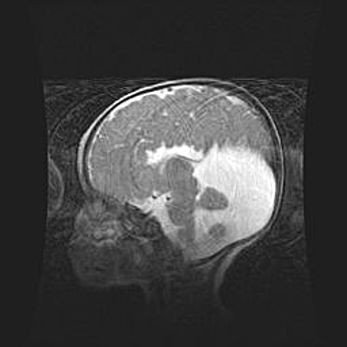

Лейкомаляция с кистозно-глиозной дегенерацией головного мозга.

Возраст: 2 месяца 25 дней

Вес: 6400 г

Окружность головы: 40 см

Срок гестации: 41 неделя

Лейкомаляцию относят к ишемически-гипоксическим повреждениям головного мозга, диагностируемым у новорожденных. При лейкомаляции в головном мозге обнаруживают очаги некроза, возникшие после тяжелой гипоксии и нарушения кровотока. В процессе морфогенеза очаги проходят три стадии: 1) развития некроза, 2) резорбции и 3) формирования глиозного рубца или кисты. Перивентрикулярная лейкомаляция (ПЛ) встречается примерно в 12% случаев среди новорожденных, обычно – у недоношенных детей, причем, частота ее зависит от массы, с которой младенец появился на свет. Наибольшее число малышей страдает лейкомаляцией, если масса при рождении 1500-2500 г.